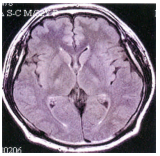

53 由所附之 MRI 腦部影像,可知是何種影像?

(A) T1WI(T1 weighted images)(B) T2WI(T2 weighted images)(C) FLAIR(Fluid-attenuated inversion recovery)(D) DWI(diffusion weighted images)